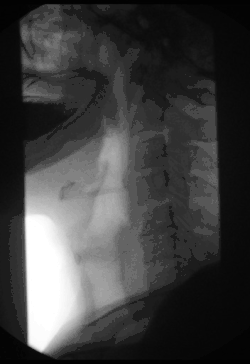

Gastrointestinal fluoroscopy

Fluoroscopy can be used to examine the digestive system using a substance that is opaque to X-rays (usually barium sulfate or gastrografin), which is introduced into the digestive system either by swallowing or as an enema. This is normally as part of a double-contrast technique, using positive and negative contrast. Barium sulfate coats the walls of the digestive tract (positive contrast), which allows the shape of the digestive tract to be outlined as white or clear on an X-ray. Air may then be introduced (negative contrast), which looks black on the film. The barium meal is an example of a contrast agent swallowed to examine the upper digestive tract. While soluble barium compounds are very toxic, the insoluble barium sulfate is nontoxic because its low solubility prevents the body from absorbing it. Investigations of the gastrointestinal tract include barium enemas, defecating proctograms, barium meals and swallows, and enteroclysis.[8]